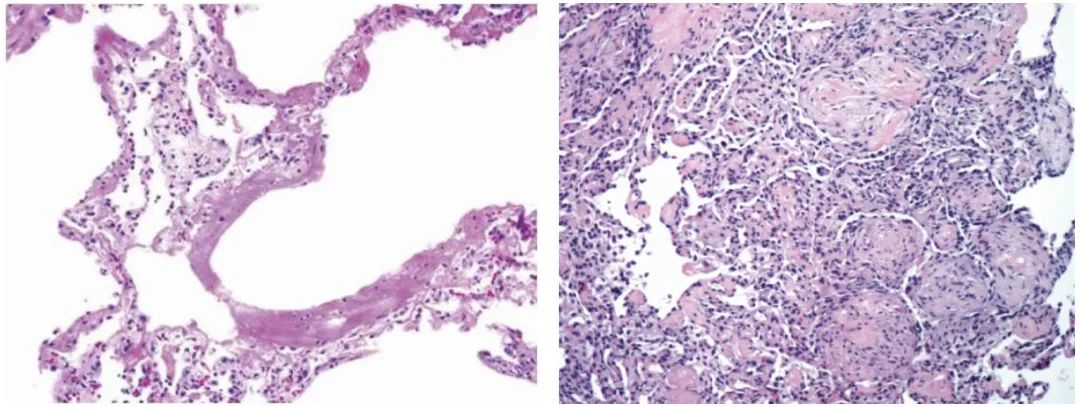

• 流感病毒肺炎的病理学

流感病毒主要感染呼吸道上皮,导致呼吸道粘膜坏死脱落【图7】;也可累及肺部,表现为肺泡上皮损伤、肺泡壁毛细血管扩张、淤血,肺泡间隔增宽、淋巴细胞浸润,Ⅱ型肺泡上皮细胞增生【图8】。肺泡腔内炎性渗出、严重者可形成局部或弥漫性的透明膜【图9】。愈合期以间质淋巴细胞浸润和支气管上皮鳞状化生为特征。流感病毒感染通常没有病毒包涵体。机化性肺炎也是流感病毒肺炎的一种表现形式【图10】,此类患者临床上需要加用糖皮质激素治疗。

图7                                                                                                              图8

图9                                                                                                              图10